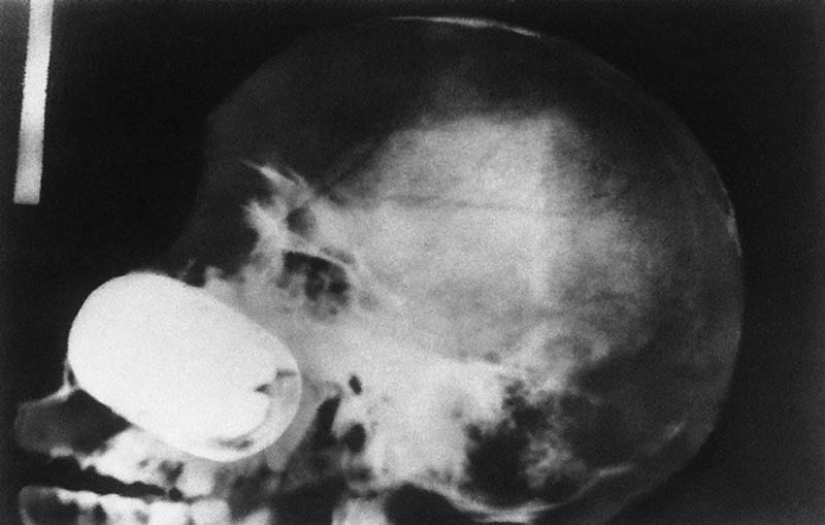

16. Una granada en el cráneo del prisionero.